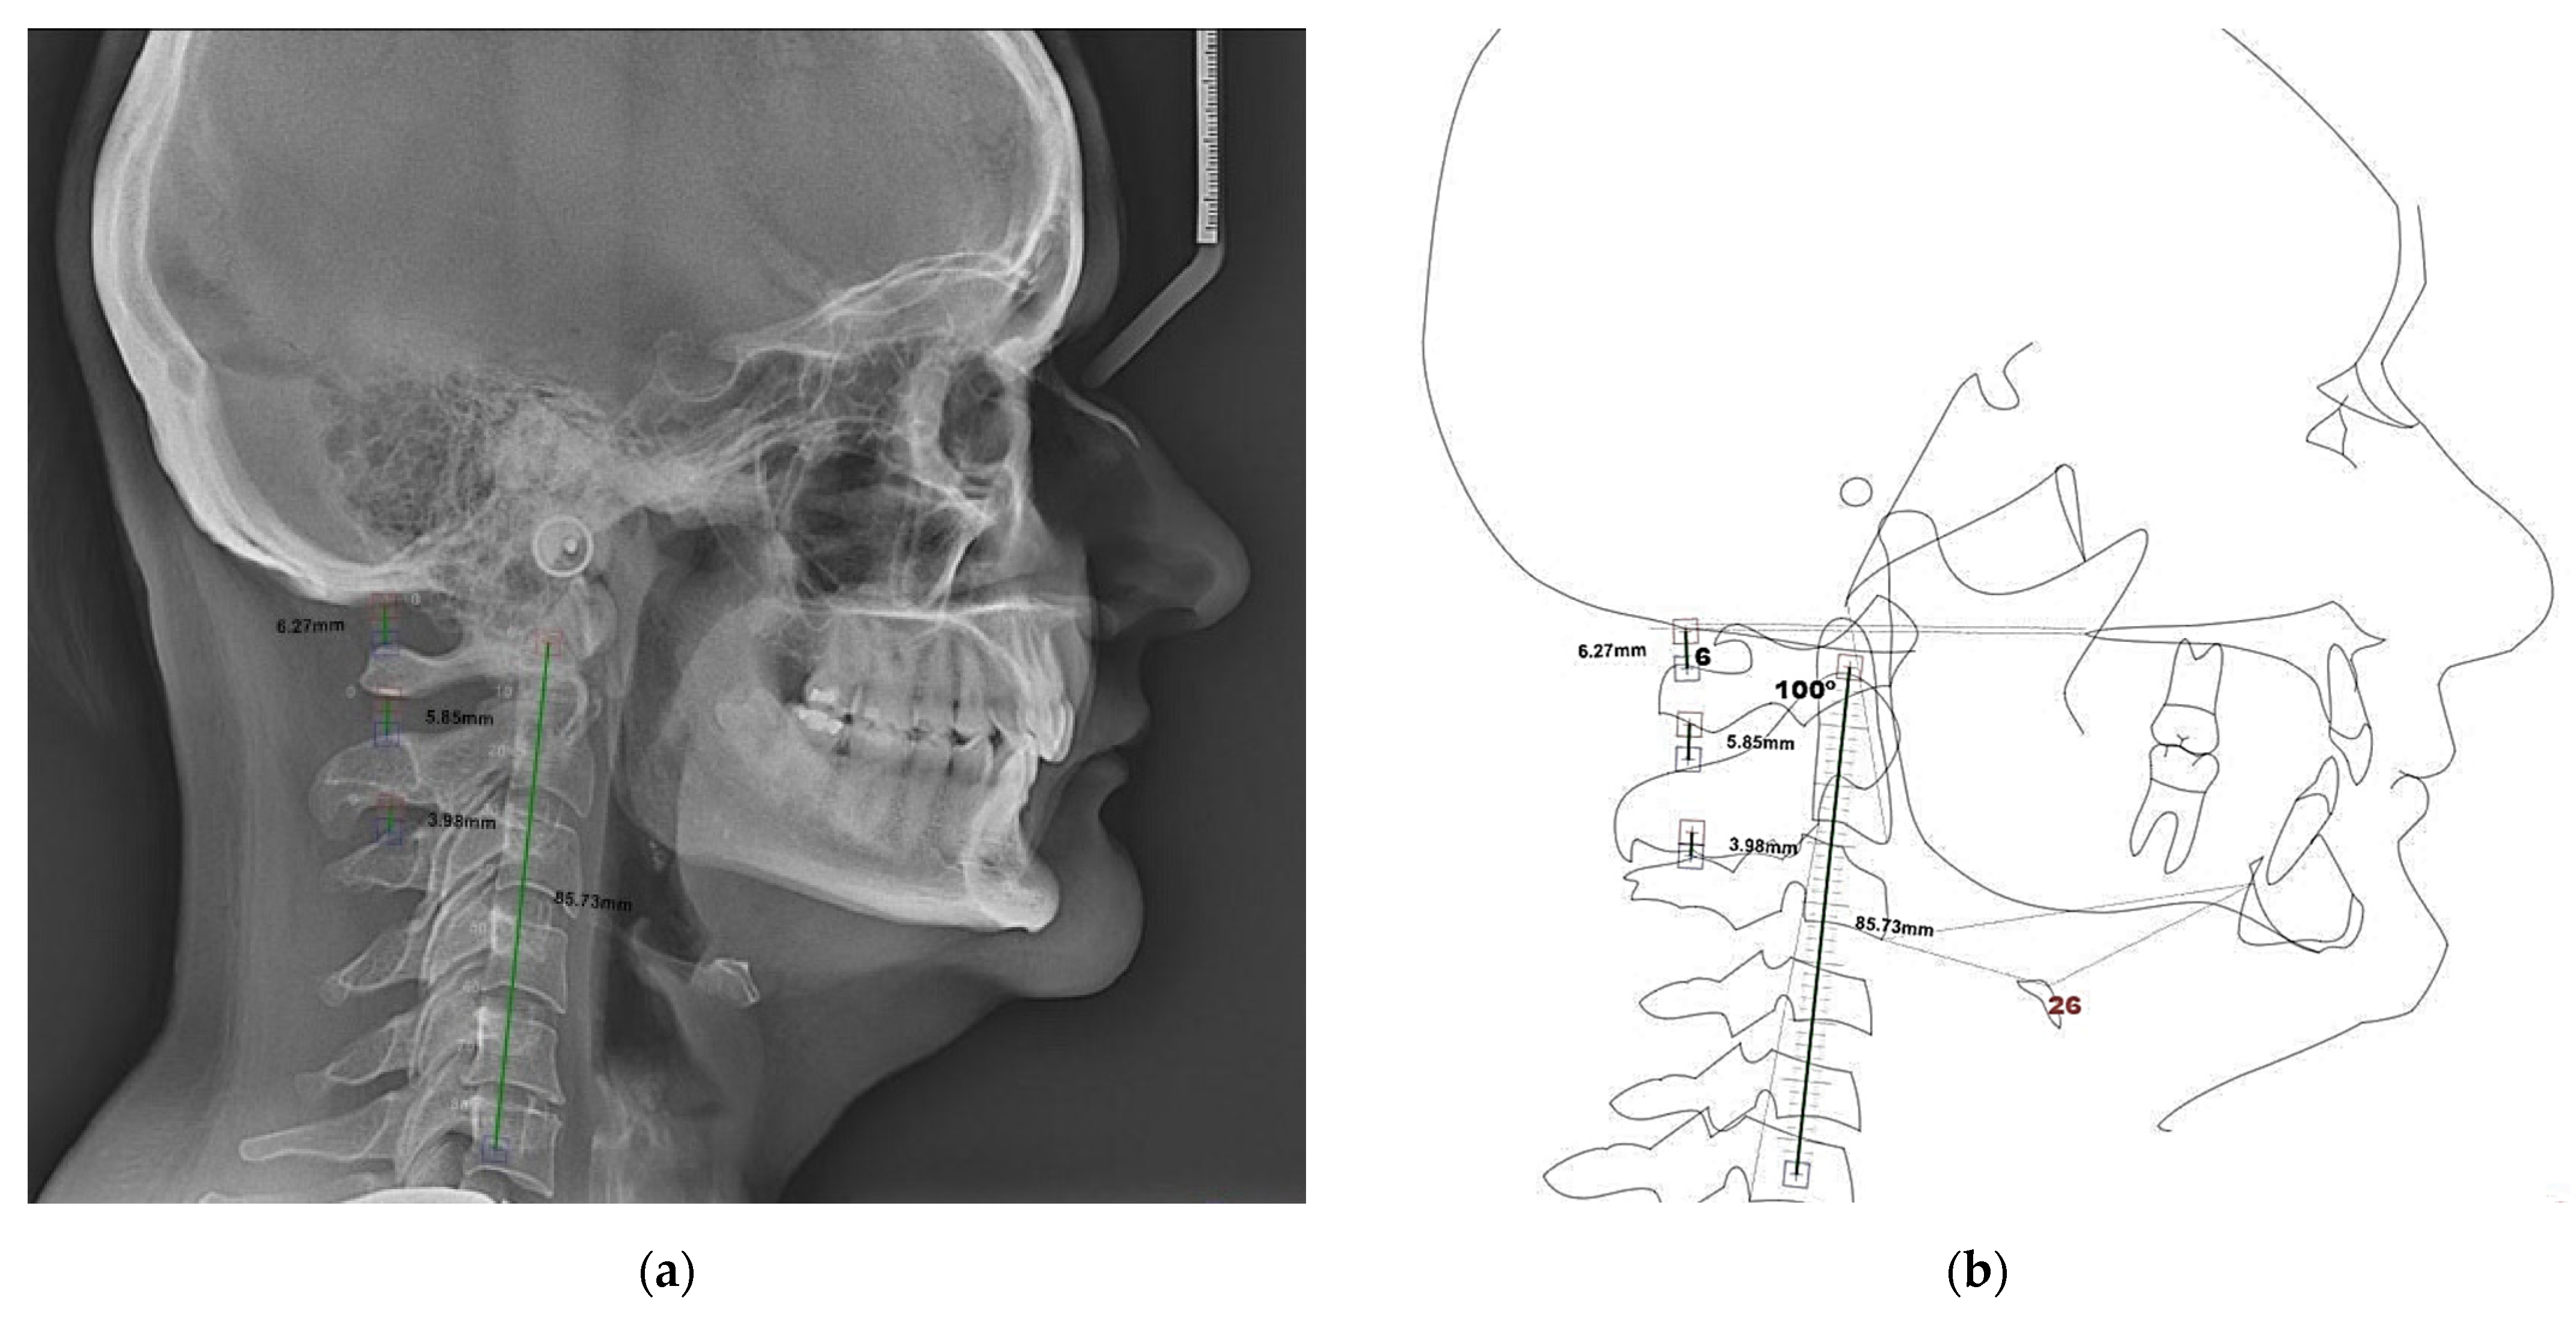

| Parameter | Value | Mean ± SD | Meaning |

|---|---|---|---|

| SNA | 86.5° | 82 ± 2° | protruded maxilla |

| SNB | 83° | 80 ± 2° | prognathic mandible |

| Y axis to S-N | 60° | 70 ± 4° | horizontal growth pattern |

| FMA | 11.5° | 25 ± 2° | hypodivergent pattern |

| gonial angle | 109° | 125 ± 5° | acute gonial angle |

| occlusal plane to Go-Gn | 2.7° | 19.09 ± 4.7° | vertical undergrowth of mandible |

| occlusal plane to S-N | 16.3° | 14.5 ± 2° | horizontal growth tendency |

| S-N to Gn | 59.5° | 67.0 ± 2° | hypodivergent facial pattern |

| S-N to Go-Me | 16.5° | 32 ± 2° | horizontal growth tendency |

| articular angle | 141° | 145 ± 5° | acute articular angle |

| facial height ratio | 83.48% | 65 ± 8% | hypodivergent growth pattern |

| lower anterior facial height (mm) | 98.5 mm | 130 ± 3 mm | small anterior facial height |

| Go-Gn (mandibular plane) to S-N | 13.6° | 32 ± 4° | hypodivergent facial pattern |

| Wits appraisal | −0.5 mm | −2.5 ± 0.5 mm | skeletal class II |

| A-B plane | −7.5 mm | −4.5 ± 2.5 mm | class II malocclusion |

| overbite | 3.5 mm | 2 ± 2 mm | normal |

| overjet | 3.5 mm | 2 ± 2 mm | normal |